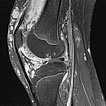

Here, sagittal view of an MRI (T2-weighted with fat saturation) of the right knee. The venous malformation is clearly hyperintense (white in the image) and extends intra-articularly into the joint space. In addition, extensive cartilage damage.